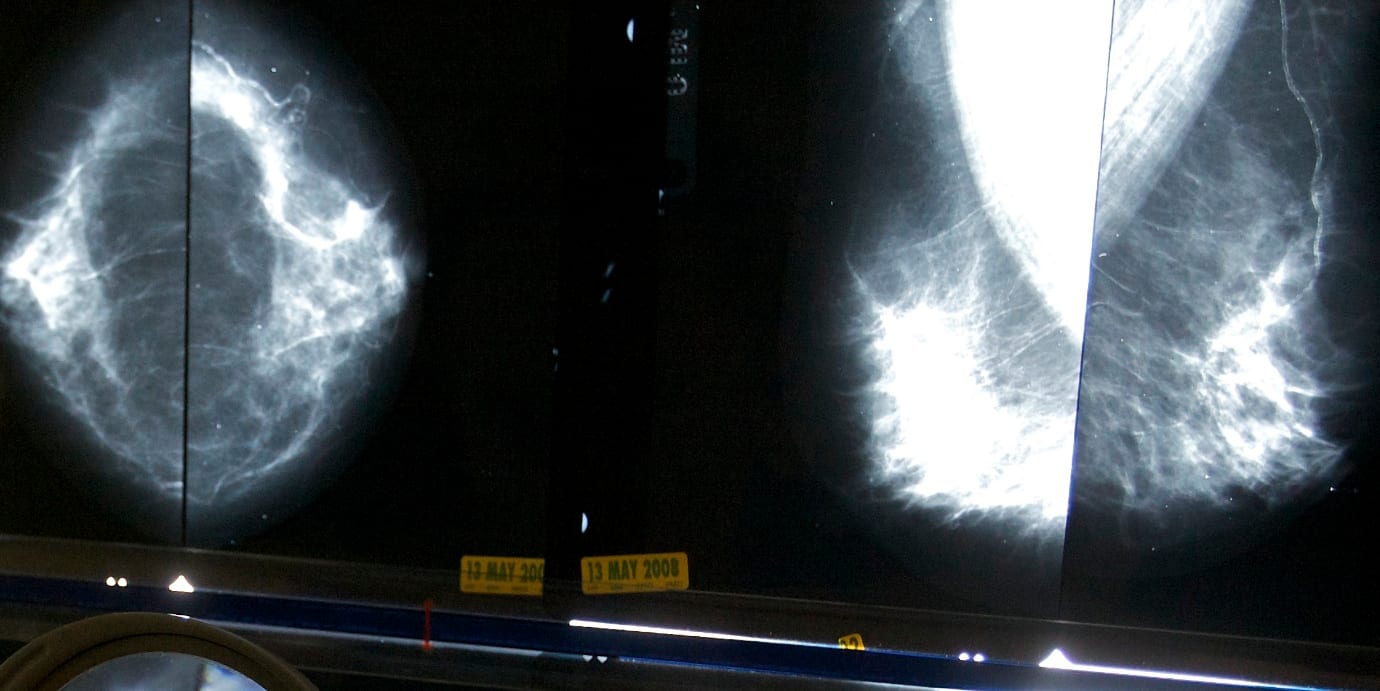

Långa cancerköer riskerar patientens liv

Landstingens långa cancerköer är en fara för patienternas liv, säger cancerläkaren Roger Henriksson, ordförande för Sveriges onkologer, till SVT Nyheter. Många landsting brottas med långa köer och vissa klarar inte av att behandla alla cancersorter på grund av väntetiderna, visar SVT:s granskning.